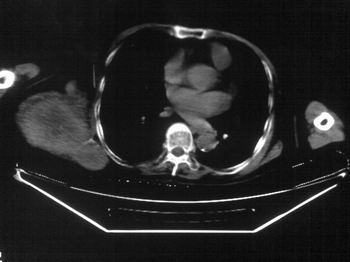

以下是引用zhangxu5888在2007-9-11 16:25:00的发言:[br]有侧肩胛骨溶骨性破坏且见软组织成分,增强软组织强化明显,中央见低密度坏死区!根据病史10年,考虑良性肿瘤恶性变!性质待定!

以下是引用老爱克斯新网客在2007-9-11 18:22:00的发言:[br]应该是良性肿瘤恶变,但因晚期破坏严重不能见到原来肿瘤征象无法判断,